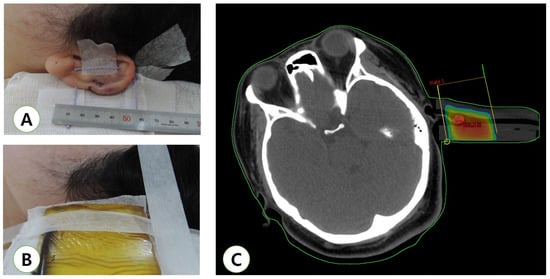

4. Radiation Technique

- Lin, Y.F.; Shueng, P.W.; Roan, T.L.; Chang, D.H.; Yu, Y.C.; Chang, C.W.; Kuo, A.T.; Chen, Y.S.; Hsiao, H.W.; Tien, H.J.; et al. Tomotherapy as an Alternative Irradiative Treatment for Complicated Keloids. J. Clin. Med. 2020, 9, 3732. [Google Scholar] [CrossRef]

- Hsueh, W.T.; Hung, K.S.; Chen, Y.C.; Huang, Y.T.; Hsu, C.K.; Ogawa, R.; Hsueh, Y.Y. Adjuvant Radiotherapy After Keloid Excision: Preliminary Experience in Taiwan. Ann. Plast. Surg. 2019, 82, S39–S44. [Google Scholar] [CrossRef]